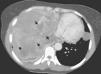

Imaging tests were ordered and chest radiography (Fig. 1A and B, arrows) showed a homogenous opacity on the right side that affected most of the right lung, with pleural effusion, deviation of the trachea toward the left and two coin-shaped opacities in the left lung field (arrows). An additional imaging test, chest computed tomography (CT) (Fig. 2), revealed the presence of a large heterogeneous mass with multiple foci of necrosis (arrow tips) and collapse of the right lung. The two coin-shaped lesions observed on the chest radiograph in the left lung were confirmed by CT. The mediastinum was deviated toward the left, with no significant lymphadenopathies.